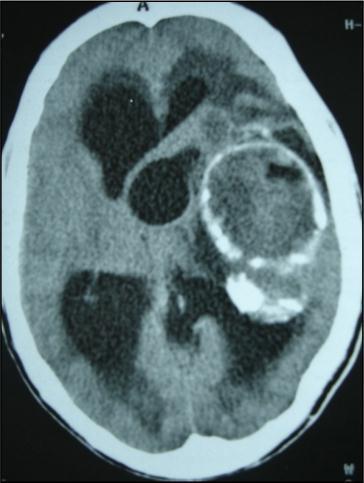

A 27 years-old male patient was admitted with 1 month history of headache, fever, short term memory lack, aphasia, right hemiparesis and seizures. He had liver hydatid cysts excised 8 years before and was treated with adjuvant medication (albendazole). The neurological examination revealed right central third cranial nerve palsy and hemi paresis, with Babinski sign positive, aphasia and papilledema on ocular fundus. The Glasgow Coma Scale was evaluated to 10/15 (E:3; V:1; M:6). A brain CT scan showed a large left temporoparietal intracerebral multiple and calcified hydatid cysts, important mass effect with midline shift about 7 mm following by an obstructive hydrocephalus (Figure 1). Other cysts were found in thalamic region (Figure 2). The Thoraco-abdominal CT scan showed multiple intra peritoneal hydatid cysts (Figure 3). A left temporo parietal craniotomy was performed in emergency. After corticectomy, using Arana-Iniguez technique, the appearance of the capsule suggested infected hydatid cysts with a purulent material which was aspirated. Numerous hydatid cysts were lifted away and several daughter vesicles were carefully removed without rupture (Figure 4). Macroscopically, the abscess wall appeared to be thick, calcified and tightly attached to lateral ventricular, so it could not be removed. The deep cyst overlying the third ventricle was left.in place. Microscopic examination demonstrated live scoleces, protoscoleces and multiple hooks. These findings are consistent with hydatid cyst (granulosis ecchinococcus) (Figure 5). Bacteriology examination found several white blood cells in the pus (neutrophilia) and infection by streptococcus pneumonia. This was consistent with infection. After surgery, the patient had medication (albendazole, specific antibiotherapy and phenobarbital). The inflammation assessment in the blood showed leukocytosis, a high C-reactive protein rate and increased erythrocyte sedimentation rate. Post operative CT scan was performed and showed the residual calcified capsule and decreased ventricular size (Figure 6). Clinical improvement was achieved after treatment. One month after the initial diagnosis, CT scan of the brain showed no recurrence and a physical examination revealed a neurologically intact, fully functional patient and eyes fundus normal. He was discharged and went to abdominal surgery two months later with complete intra abdominal cysts removal. Albendazole treatment was continuing for six months and radiological exploration was performed by brain MRI with spectroscopy at three and six month later. This showed that infection had resolved and the deep cyst overlying the third ventricle is less spherical (Figure 7, Figure 8). Four years later, the outcome was good.

Figure 2.axial CT showing another cyst located in thalamic region